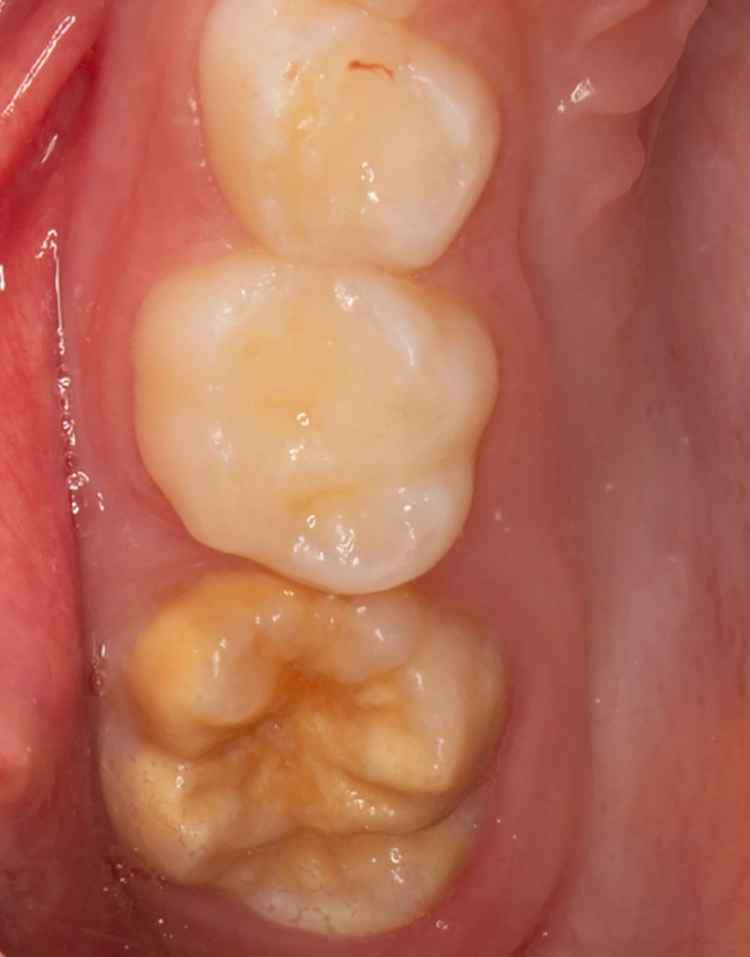

Komposit

Bekes/BoukhobzaAbb. 5a–c: Posteruptiver Schmelzverlust und Kavitation an dem unteren bleibenden MIH-Molaren und anschließende

Füllungstherapie mit einem Komposit.

Aufgrund seiner Eigenschaften ist Komposit das geeignetste und zu favorisierende direkte Restaurationsmaterial bei MIH-Zähnen [14]. Es bedarf keiner retentiven Präparation, sodass die Füllung gezielt defektorientiert gelegt und der umliegende gesunde Schmelz geschont werden kann (Abb. 5a–c). In einigen Studien konnte gezeigt werden, dass Self-Etch-Adhäsive signifikant bessere Haftwerte an MIH-Zähnen ergeben als Total-Etch-Systeme und somit mindestens gleichwertig, wenn nicht überlegen sind.

Bekes/BoukhobzaHieraus folgend kann laut dieser Studien der Konditionierungsschritt übersprungen werden [15,16]. Trotzdem liegt die Schmelzhaftung aller Dentinadhäsive an hypomineralisiertem Schmelz weiterhin unter der weitaus höheren Schmelzhaftung an gesunden Zähnen. Eine weitere Schwierigkeit in der restaurativen Versorgung von hypomineralisierten Zähnen bereitet die Bestimmung und Einschätzung der genauen Ausdehnung der geplanten Restauration.

Der Füllungsrand sollte unter idealen Verhältnissen in gesundem Schmelz enden, um weitere Schmelzeinbrüche oder einen Füllungsverlust zu vermeiden, da der adhäsive Verbund zu hypomineralisiertem Schmelz verringert ist [15]. Dies ist klinisch jedoch nicht immer praktikabel.